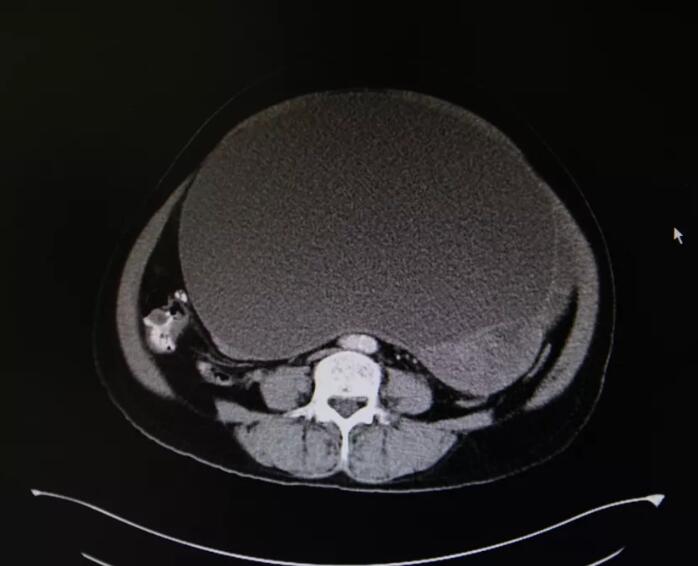

在門診初見陳阿姨時,王建南就判定她腹腔內(nèi)有腫瘤包塊,根據(jù)影像學(xué)檢查結(jié)果,他判斷該腫瘤以實性成分為主, “由于腫塊巨大,占據(jù)了盆腹腔絕大部分空間,好在腫瘤有腹膜包著手術(shù)風(fēng)險相對要小一點?!?/p>

王建南教授提到,陳阿姨的盆腹腔腫塊來源于子宮底部,屬于畸胎瘤, “腫瘤與子宮間有較致密黏連,幸運的是與腹腔及腸管無粘連,但腫瘤的體積大還是給手術(shù)增加了難度?!?/p>

上午九點,王建南教授團(tuán)隊小心翼翼開始為陳阿姨實施手術(shù)。在她的腹正中先切一長15cm切口,切開皮膚、皮下、腹直肌、腹膜,探查腹腔,可見一巨大腫瘤,包膜完整,沿原切口向上方延長切口至劍突下,可見腫瘤大小約20cm×20cm×20cm,形態(tài)較規(guī)則,腫瘤下方觸及與子宮底粘連,用止血鉗鉗夾腫瘤根部,將腫瘤及部分子宮底完整切除,將腫瘤完好無損地搬離盆腔,將復(fù)雜的手術(shù)變得簡單,最后利落干凈地將部分子宮底完整切除。術(shù)中出血僅30ml,在場醫(yī)護(hù)人員都贊嘆不已。切除的腫瘤標(biāo)本重達(dá)15多斤,用7號線縫扎殘端,再次探查腹腔未見明顯出血,留置盆腔引流管一根,逐層關(guān)腹。